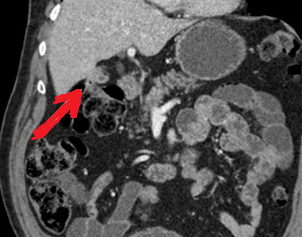

Polycystic liver disease. Red arrow. Infected hepatic cyst (Courtesy Dr. V. Penopoulos)